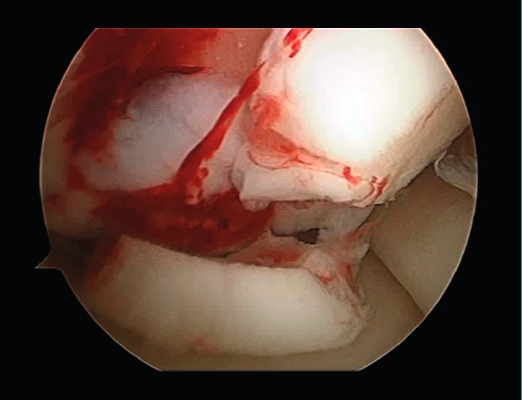

- The damaged cartilage is cleaned using curettes, with debridement of the defect, and the lesion is left with healthy and exposed subchondral bone (Figure 7).

Figure 7. Debridement of the damaged cartilage.